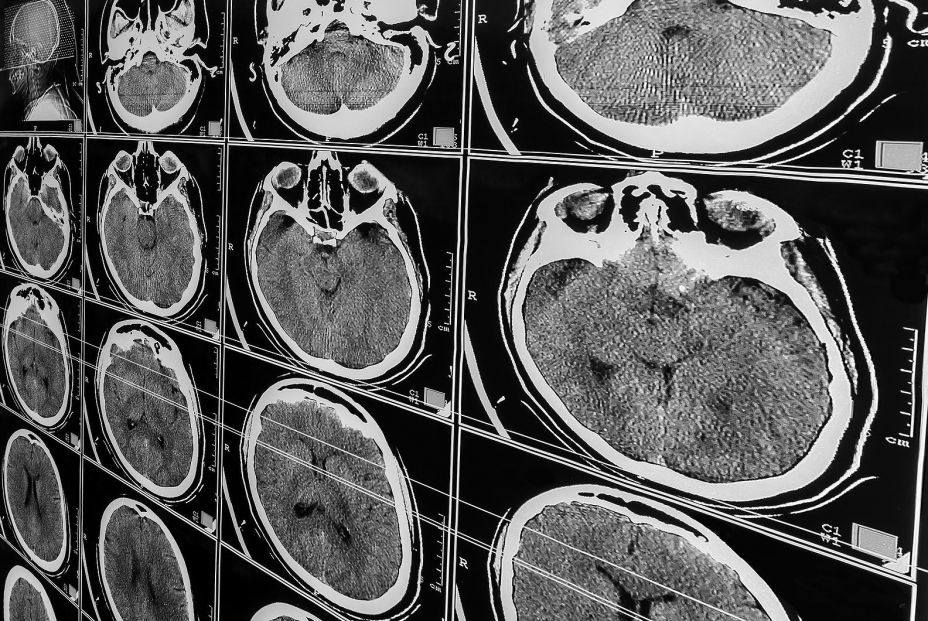

Sabemos que el El alzhéimer (EA) es una enfermedad neurodegenerativa que supone la primera causa de demencia a nivel mundial. Se estiman unos 40 millones de personas en el mundo afectadas de demencia atribuible a ella. En España, según datos de la Sociedad Española de Neurología (SEN), podrían existir unas 800.000 personas con esta patología.

En la segunda parte de su estudio, analizaron los cerebros post mortem de 578 participantes. Descubrieron que quienes comían uno o más huevos a la semana tenían mayor probabilidad de presentar una menor acumulación de proteínas asociadas al Alzheimer.